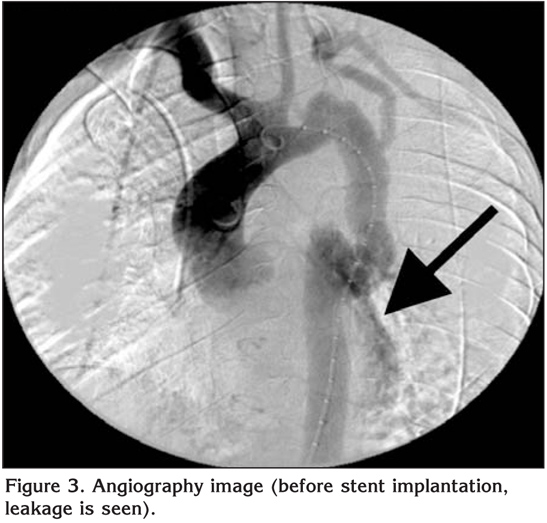

Surgical treatment can be considered as a treatment choice as well as intravascular stent implantation. In the HRCT of thorax and in the angiography, a blood leakage from graft to bronchial system can be seen. However, after the stent implantation, it's observed that the leakage completely stopped (Figure 3,4).

Figure 3